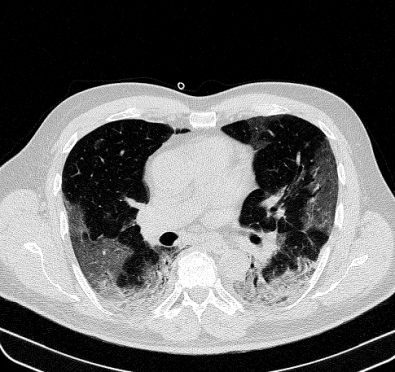

Lung segmentation results for the polymorphic and nonpolymorphic models are shown in Figure 3. Quantitative evaluation of lung segmentations was performed on CT images by comparing the segmentations to ground truth manual segmentations. The Dice coefficient was used to measure volume overlap and the average symmetric surface distance (ASSD) was used to assess boundary accuracy. The ASSD and Dice coefficient results for each of the four evaluation datasets are shown in Table 2. Overall, on the COVID-19 dataset the polymorphic model achieved an average ASSD of mm and average Dice coefficient of . By comparison, the nonpolymorphic model achieved an average ASSD of mm and average Dice coefficient of . ASSD and Dice coefficient results with respect to nonaerated lung volume fraction are displayed in Figure 4. Two-way analysis of variance revealed a significant interaction between model and nonaerated fraction for each evaluation metric, indicating that the regression coefficients with respect to nonaerated fraction were significantly different for polymorphic vs. nonpolymorphic models.

Lobar segmentation results for the proposed method and PTK are shown in Figure 5 for right lungs and Figure 6 for left lungs. For each image in the COVID-19 dataset (133 images in total), the lobar segmentation result was used to extract the amount of poor aeration () and consolidation () in each lobe. Common phenotypes of COVID-19 affected lungs were identified by hierarchical clustering over the fraction of poorly aerated and consolidated tissue in each lobe. Dendrographic analysis in Figure 7 reveals four primary clusters of patients that were identified by the hierarchical clustering: (a) mild loss of aeration primarily in the two lower lobes without consolidation; (b) moderate loss of aeration focused in the two lower lobes with or without consolidation in lower lobes; (c) severe loss of aeration throughout all lobes with or without consolidation; and (d) severe loss of aeration and consolidation throughout all lobes.